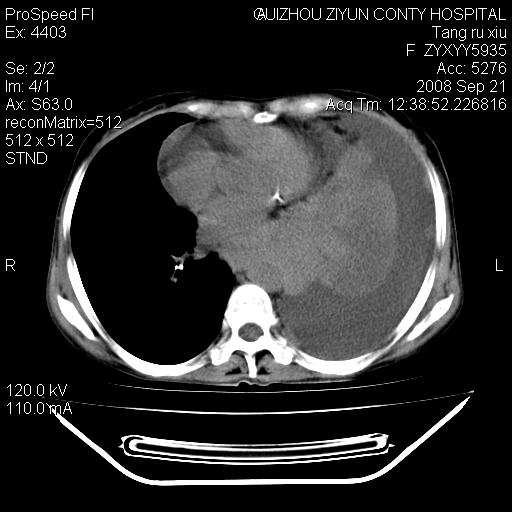

f、57岁,上腹痛.2月,近来胸闷。2月前在外院摄胸片示左侧胸腔少量积液。

(患者腹痛入院,欲吐,临床医生说禁饮,所以没有口服对比剂)

肝脏大小形态尚可,其实质内可见多发大小不等的低密度影,边缘模糊。肝门区结构紊乱,腔静脉腹主动脉旁可见多发软组织密度影,部分融合成团块状,并向下延伸。胰腺及十二指肠结构显示不清。腹腔内脐后肠管走形僵硬,管壁可见增厚。盆腔内可见多个淋巴结影。所扫层面左侧胸腔可见大量弧形水样密度影,其内侧可见被压缩的肺组织影。左侧胸壁可见一小结节样软组织密度影,边缘模糊。心脏纵隔向右侧移位。心脏包膜内可见囊样低密度影,其内侧心房室周围可见一圈气体样密度影。纵隔内大血管旁可见多发软组织团块影,部分融合。

1.腹膜后淋巴瘤侵及肝脏,肺内及纵隔内多发转移。2.左侧大量胸腔积液并压缩性肺不张。3.心包脓肿可能,转移不除外。4.脐后局部肠管管壁增厚,考虑炎症可能,肿瘤不除外。

左侧中心型肺癌并胸膜及心包转移。肝内转移,腹膜后淋巴结转移。